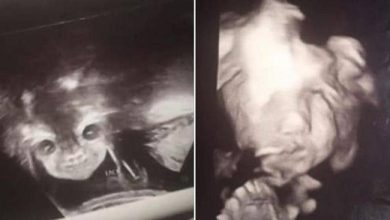

” الجنين الشيطان ” يثير قلق والديه .. و الطب يوضح الحقيقة